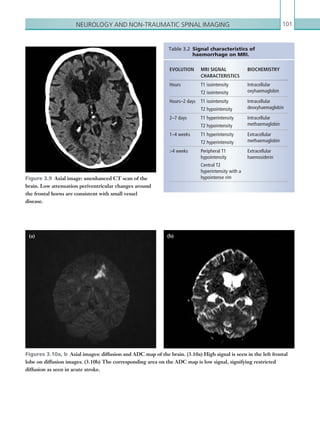

• 212.

• 213.

191 Chapter 6 INTERVENTIONAL AND­VASCULAR IMAGING AND IATROGENIC ­COMPLICATIONS ACUTE ARTERIAL ISCHAEMIA Acute arterial occlusion in an extremity must be treated as a medical/surgical emergency as there is not only danger to the limb, but also to the life of the patient. Generally this condition occurs in elderly patients with multiple comorbidities. Acute arterial occlusion can be the result of a proximal embolus lodging in a more distal vessel, acute thrombosis of a previously patent artery, acute thrombosis of a stent or graft, dissection of an artery or direct trauma to an artery. The most common source of embolism is the heart; for example, from thrombus within an LV aneurysm (Figure 6.1) or secondary to arrhythmias. Arterio- arterial emboli can arise from aneurysms or from non-occlusive, ulcerated atheromatous plaques. Acute in-situ thrombosis occurs mostly at sites of stenotic arteriosclerotic lesions. Other causes of arterial thrombosis include ­pro-thrombotic states such as recent trauma/surgery, pregnancy, cancer, reversal of anticoagulation,nephroticsyndromeandinflammatory bowel disease. Presentation with acute arterial ischaemia is most commonly seen in the lower limbs and characterised by ‘the 6 P’s: pain, pallor, pulselessness, paraesthesia, paralysisandpoikilothermia(i.e.coldness).Paraesthesia and paralysis imply irreversible ischaemia, and muscle rigidity is a sign of a non-salvageable limb. With acute occlusion of central blood vessels such as the aorta, iliac or femoral arteries, there is complete ischaemia with onset of rhabdomyolysis after four to six hours; this can lead to severe local and generalised symptoms because of the dangerous metabolites released. Radiological investigations Ultrasoundcanbeusedfortheassessmentofperipheral arterial flow, especially in the arms and legs. Doppler or duplex scanning can assess arterial flow patterns to assess for thrombosis. In the acute setting, however, the availability of expertise in duplex scanning is relatively rare. Figure 6.1  Axial image: IV contrast enhanced CT scan of the chest in the arterial phase. The non-enhancing filling defect (arrow) in the left ventricle is ­consistent with LV thrombus. There is thinning of the LV ­myocardium at the apex due to a previous infarct. K22247_C006.indd 191 16/05/15 3:12 AM

• 214.

Chapter 6192 Figure 6.2 Axial image: IV contrast enhanced CT scan of the lower limbs in the arterial phase. The lumen of the right superficial femoral artery does not opacify with contrast, while the corresponding artery on the left does. No collateral vessels are seen around the right superficial femoral artery, suggesting acute arterial thrombosis. Figure 6.3  Axial image: IV contrast enhanced CT scan of the pelvis in the arterial phase. An intraluminal filling defect can be seen in the right common iliac artery (arrow). A small amount of peripheral enhancement is seen around the periphery of the occluded vessel. MODALITY PROTOCOL CT Angiogram: 100 ml IV contrast via 18G cannula, 4 ml/sec. Bolus track centred on the descending thoracic aorta (if assessing lower limbs)/centre on ascending aorta (for upper limbs). Scan from just above aortic arch to ankles for lower limbs or C2 to hands depending on side. Table 6.1 Acute arterial ischaemia. ­Imaging  protocol. CTA is the imaging modality of choice in the acute setting to assess the vasculature for acute arterial thrombosis or embolus. The protocol varies depending on whether the lower or upper limbs are affected. (See Table 6.1.) Radiological findings Computed tomography A good CTA enables the radiologist to fully assess the arterial tree; however, windowing may be useful to reduce the glare from the bright contrast within the vessel and therefore allow more accurate assessment. The blood vessels must be carefully scrutinised from a proximal to distal direction. It is important to first assess the heart for valve abnormalities, such as vegetation or thrombus within any of the cardiac chambers. The whole aorta should then be assessed for the presence of any aneurysms. If an aneurysm is present, comment should be made as to the amount of intramural thrombus and also as to whether there is any leak. All the major vessels should be assessed carefully in a systematic fashion, one side at a time. Features suggestive of acute arterial occlusion are an abrupt cut-off of the arterial opacification, with a lack of surrounding collaterals (Figure 6.2). In the acute thrombosis, the presence of clot leads to a smooth but abrupt cut-off. The affected arteries may be expanded with clot and may show subtle peripheral enhancement (Figure 6.3). K22247_C006.indd 192 16/05/15 3:12 AM

• 215.

Interventional and ­vascularimaging and iatrogenic ­complications 193 IATROGENIC COMPLICATIONS Iatrogenic complications of medical interventions are relatively commonplace and occur across many facets of medical practice. These may be related to routine procedures that may have minimal clinical significance to the patient (e.g. bruising following venepuncture), but can also have significant and potentially life- threatening consequences for patients. Some of these are particularly pertinent to radiologists either because of the frequency of errors that may be avoided by thorough radiological interpretation or because they may be may be related to common interventional radiologyprocedures.Thefollowingsectionhighlights some of the commonest complications that may be encountered. NASOGASTRIC TUBE MISPLACEMENT ReducingtheharmcausedbymisplacedNG tubeswasa Patient Safety Alert published by The National Patient SafetyAgency(NPSA)in2005.InthereporttheNPSA provided guidance for checking and confirming that an NG tube had been inserted into the correct place (i.e. the stomach). After placement, an NG tube is aspirated and the aspirate tested on litmus paper to confirm that it is acidic (i.e. gastric aspirate). Inpatientswhoaresedated,haveapoorcoughreflex, are intubated or agitated there is increased risk of tube misplacement. This can lead to severe complications such as pneumonia, pneumothorax, empyema and pulmonary haemorrhage. It is useful to assess the vessels using multiplanar reformats. The length, extent and number of vessels involved should be reported. Distal filling and quality of blood vessels beyond the occlusion should be commented on as these have implications for management. Treatment is either by vascular surgery or interventional radiology. It is often difficult to distinguish between acute and chronic occlusions; however, the clinical history should be noted, as this is a key factor in deciding between the two. The presence of collateral vessels can imply chronicity. Arterial thrombus may be present in central vessels in patients with pro-thrombotic states. Careful assessment of the aorta and its branches is important as well as assessment of visceral enhancement of bowel, kidneys, etc. Key points • Where patients present with the 6 P’s, there is limited time to salvage the leg. There should be no delays in organising a CTA for these patients in order to assess the arterial tree. • A systematic approach is always best when assessing vasculature; this can be proximal to distal and one side then the other. Coronal reformats can be very useful. • Acute thrombus results in a smooth, abrupt cut-off of the arterial opacification with a lack of collaterals. The affected vessel may be expanded and show some peripheral enhancement. Report checklist • The quality of vessels proximal and distal to any occlusion; whether they are patent and/or how good they are. This has implications for management options such as bypass/thrombolysis. • Degree of collateralisation. • Recommend urgent vascular surgical opinion. K22247_C006.indd 193 16/05/15 3:12 AM

• 216.

Chapter 6194 Figure 6.5 PA chest radiograph. A nasogastric tube is seen passing into the right lower lobe bronchus and coiled in the right lower zone. An endotrached tube is also sited. Figure 6.4  PA chest radiograph. A nasogastric tube is seen passing centrally and coursing to the left under the left hemidiaphragm. A tunnelled left-sided central line is also noted. Radiological investigations Plainfilmimagingofthechestisusuallyadequatewhere aspiration is not possible or there is concern regarding the position of the NG tube tip. (See Table 6.2.) Radiological findings Plain films NG tubes vary in type and opacity. Some tubes are opaque throughout their length, whereas some only havearadiopaquetip.AnormalNGtubeshouldcourse centrally through the thorax and lie with the tip below the left hemidiaphragm (Figure 6.4). NG tubes that do not follow this path may be within a bronchus or coiled in the oesophagus (Figures 6.5–6.7). Particular attention should be paid to whether the path of the NG tube projects over the right or left main bronchi. Suspicion of an NG tube within the lungs should be urgently discussed with the referring team. If the NG tube is projected in the midline below the carina but not in the stomach (i.e. distal oesophagus), it can be suggested that the tube is advanced a further 5–10 cm prior to use. If the NG tube tip cannot be seen clearly, a small volume of water soluble contrast (e.g. Gastromiro) can be injected through the tube and then re-imaged to confirm the tip position. Key points • NG tubes should normally descend centrally though the thorax, with the tip seen below the left hemidiaphragm. • Misplaced NG tubes should be communicated to the clinical team in order to prevent inappropriate use. Table 6.2 Nasogastric tube misplacement. ­Imaging protocol. MODALITY PROTOCOL Plain film imaging PA CXR to include the diaphragm. Water ­soluble contrast may be injected through the nasogastric tube if the line tip is not radiopaque. K22247_C006.indd 194 16/05/15 3:12 AM